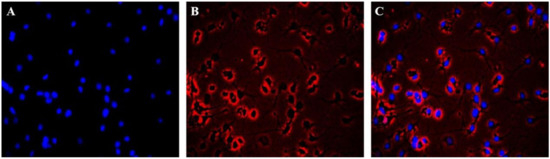

2.2. Immunofluorescence Identification of Neuronal Cells

The immunofluorescence results of Hoechst 33258 and β-III Tubulin indicated the equal distribution of neuronal cells. The cells stained with Hoechst 33258 showed blue fluorescence in the nucleus (see Figure 2A) and the cells were red fluorescence by β-III Tublin (see Figure 1B). The results showed that the neurons were evenly distributed in the whole field, but only a few of the nuclei showed no red fluorescence (see Figure 2C). The purity of the neuronal cells was greater than 95% by β-III Tublin immunofluorescence identification.

Figure 2.

Primary cultured cortical neuronal cells were identified by β-III Tubulin. (A) The nucleus was stained with Hoechst 33258. (B) Immunocytochemical signals (red) under fluorescence microscope. (C) A merged image (A and B).

4.6. Immunofluorescence Identification

The purified neuronal cells were seeded on Poly-D-lysine-treated 6-well plates and then fixed with 4% PFA for 20 min. The cells were incubated with 0.3% Triton X-100 for 20 min and 10% sheep serum for 30 min, primary antibody β-III Tubulin (1:200) overnight at 4 °C. This was followed by a secondary Goat Anti-rabbit IgG/RBITC (1:500) 37 °C for 2 h. The cells were stained with 5 mg/mL Hoechst 33258 for 30 min in the dark, then washed with PBS three times, and imaged by using a fluorescence microscope (Zeiss, Axio Vert.A1, Oberkochen, Germany) [48].